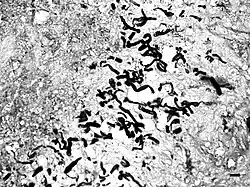

It is suspected that pythiosis is caused by invasion of the organism into wounds, either in the skin or in the gastrointestinal tract.[2] The disease grows slowly in the stomach and small intestine, eventually forming large lumps of granulation tissue. It can also invade surrounding lymph nodes. Symptoms include vomiting, diarrhea, weight loss, a mass in the abdomen, and depression. Pythiosis of the skin in dogs is very rare and appears as ulcerated lumps. Primary infection can also occur in the bones and lungs.